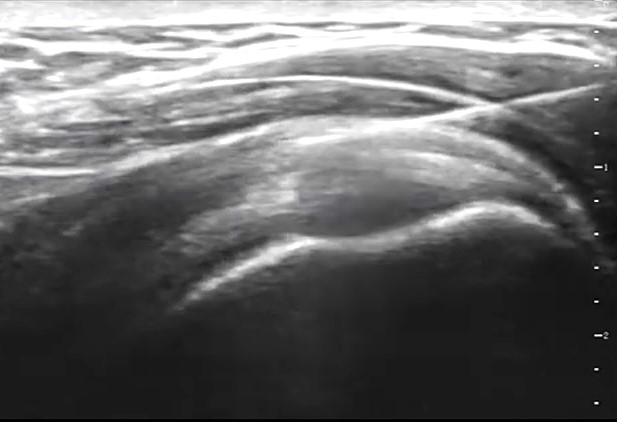

超音波検査は超音波診断装置の進歩により整形外科領域(筋・腱・靱帯・神経等)の観察・評価に非常に有用なものとなっています。超音波ガイド下により正確に患部に薬剤を注入でき整形外科治療に革命をもたらしています。

超音波診断装置について

超音波は骨のような固い組織は透過できないため骨表面の輪郭は線状高エコー像で骨内部は真っ黒に見えます。皮膚から骨までの組織は超音波が通過でき組織の性状(透過率)と構造により皮下組織・筋肉・靱帯・腱・神経・水腫・血腫などを判読します。

超音波診断①(正常肩関節)

肩の周りには最も重要な腱板という太い靱帯様組織、三角筋・棘上筋・棘下筋・肩甲下筋・上腕二頭筋腱・肩峰下滑液包などが見えます。